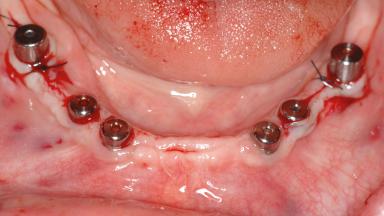

Le Fort I Interpositional Graft and Mandibular Sandwich Osteotomy for Maxillofacial Rehabilitation after Severe Periodontitis

A 47-year-old woman who had suffered from aggressive periodontitis requiring a number of periodontal interventions over more than 10 years was referred by her general dental practitioner and periodontologist for bone augmentation and implant therapy. Her failing dentition had already been scheduled for extraction. The patient expressed a desire for implant-supported fixed restorations and esthetic improvement of her lower face. She had agreed to consult with a maxillofacial surgeon after the referring dentist had suggested bone augmentation. An initial examination by the maxillofacial surgeon revealed mobility of all residual teeth in a patient who was very unhappy with the function of her removable partial dentures. Due to periodontally migrated flaring teeth and loss of occlusal support, the vertical dimension of occlusion was dramatically reduced. The patient was displeased with her lower face because of deepened nasolabial, commissural, and supramental folds.